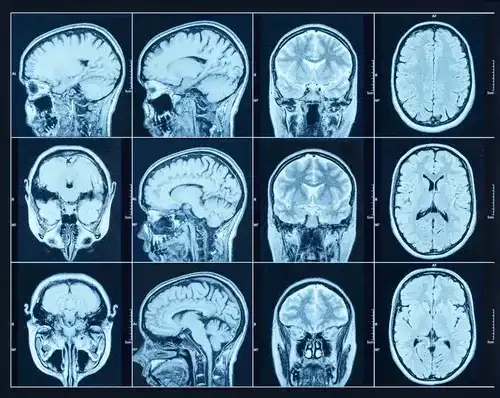

Rezonans magnetyczny głowy to niezwykle precyzyjna technika obrazowania, która wykorzystuje silne pole magnetyczne i fale radiowe do tworzenia szczegółowych obrazów struktur anatomicznych mózgu. Na obrazach MRI lekarz jest w stanie zwizualizować z wysoką dokładnością tkanki miękkie, naczynia krwionośne, płyn mózgowo-rdzeniowy oraz wszelkie zmiany strukturalne, takie jak guzy, torbiele, obszary uszkodzeń po udarach czy ogniska demielinizacyjne. Ważne jest, aby zrozumieć, że MRI pokazuje nam fizyczną architekturę mózgu. Nie jest to jednak narzędzie, które bezpośrednio "widzi" nasze myśli, emocje, wspomnienia czy samą chorobę psychiczną w sensie jej psychologicznego podłoża. Widzimy natomiast zmiany strukturalne, które mogą być z nimi skorelowane.Dlaczego psychiatra może skierować Cię na rezonans? Kluczowa rola diagnostyki różnicowej

Co naprawdę widzi lekarz na obrazie MRI Twojej głowy?